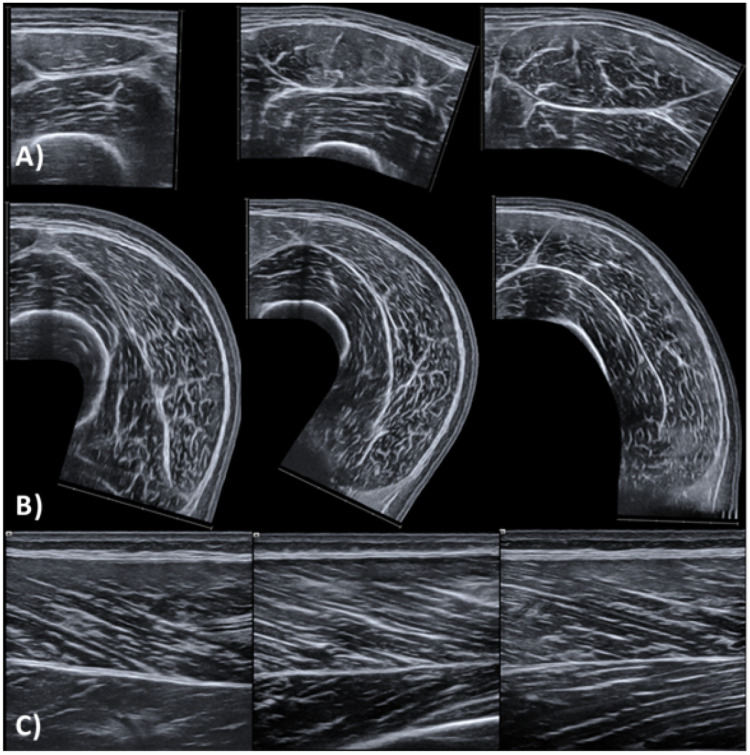

Patients and methods: We used ultrasonography to examine the regional architecture and morphology of the rectus femoris (RF) and vastus lateralis (VL) muscles, and we assessed knee extension strength by isometric and isokinetic dynamometry. Players were categorized into four age groups: under (U) 15 (n=18, age=13.7±0.5 years), U16 (n=15, age=14.7±0.5), U17 (n=19, age=15.7±0.5), U18 (n=18, age=16.7±0.5) and U21 (n=25, age=18.5±0.5).